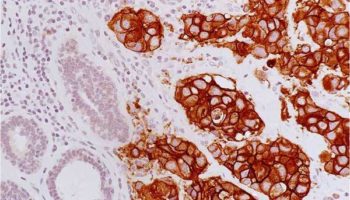

A type of laboratory test that can detect the proteins expressed by a cell. The test uses special antibodies (“immunostains”) that each binds to a particular protein in question; the immunostain will change the color of the tissue to show whether a protein is present. Examples include immunohistochemistry to look for HER-2 overexpression, as well as the expression of the estrogen receptor (ER) and progesterone receptor (PR) in breast cancer cells.